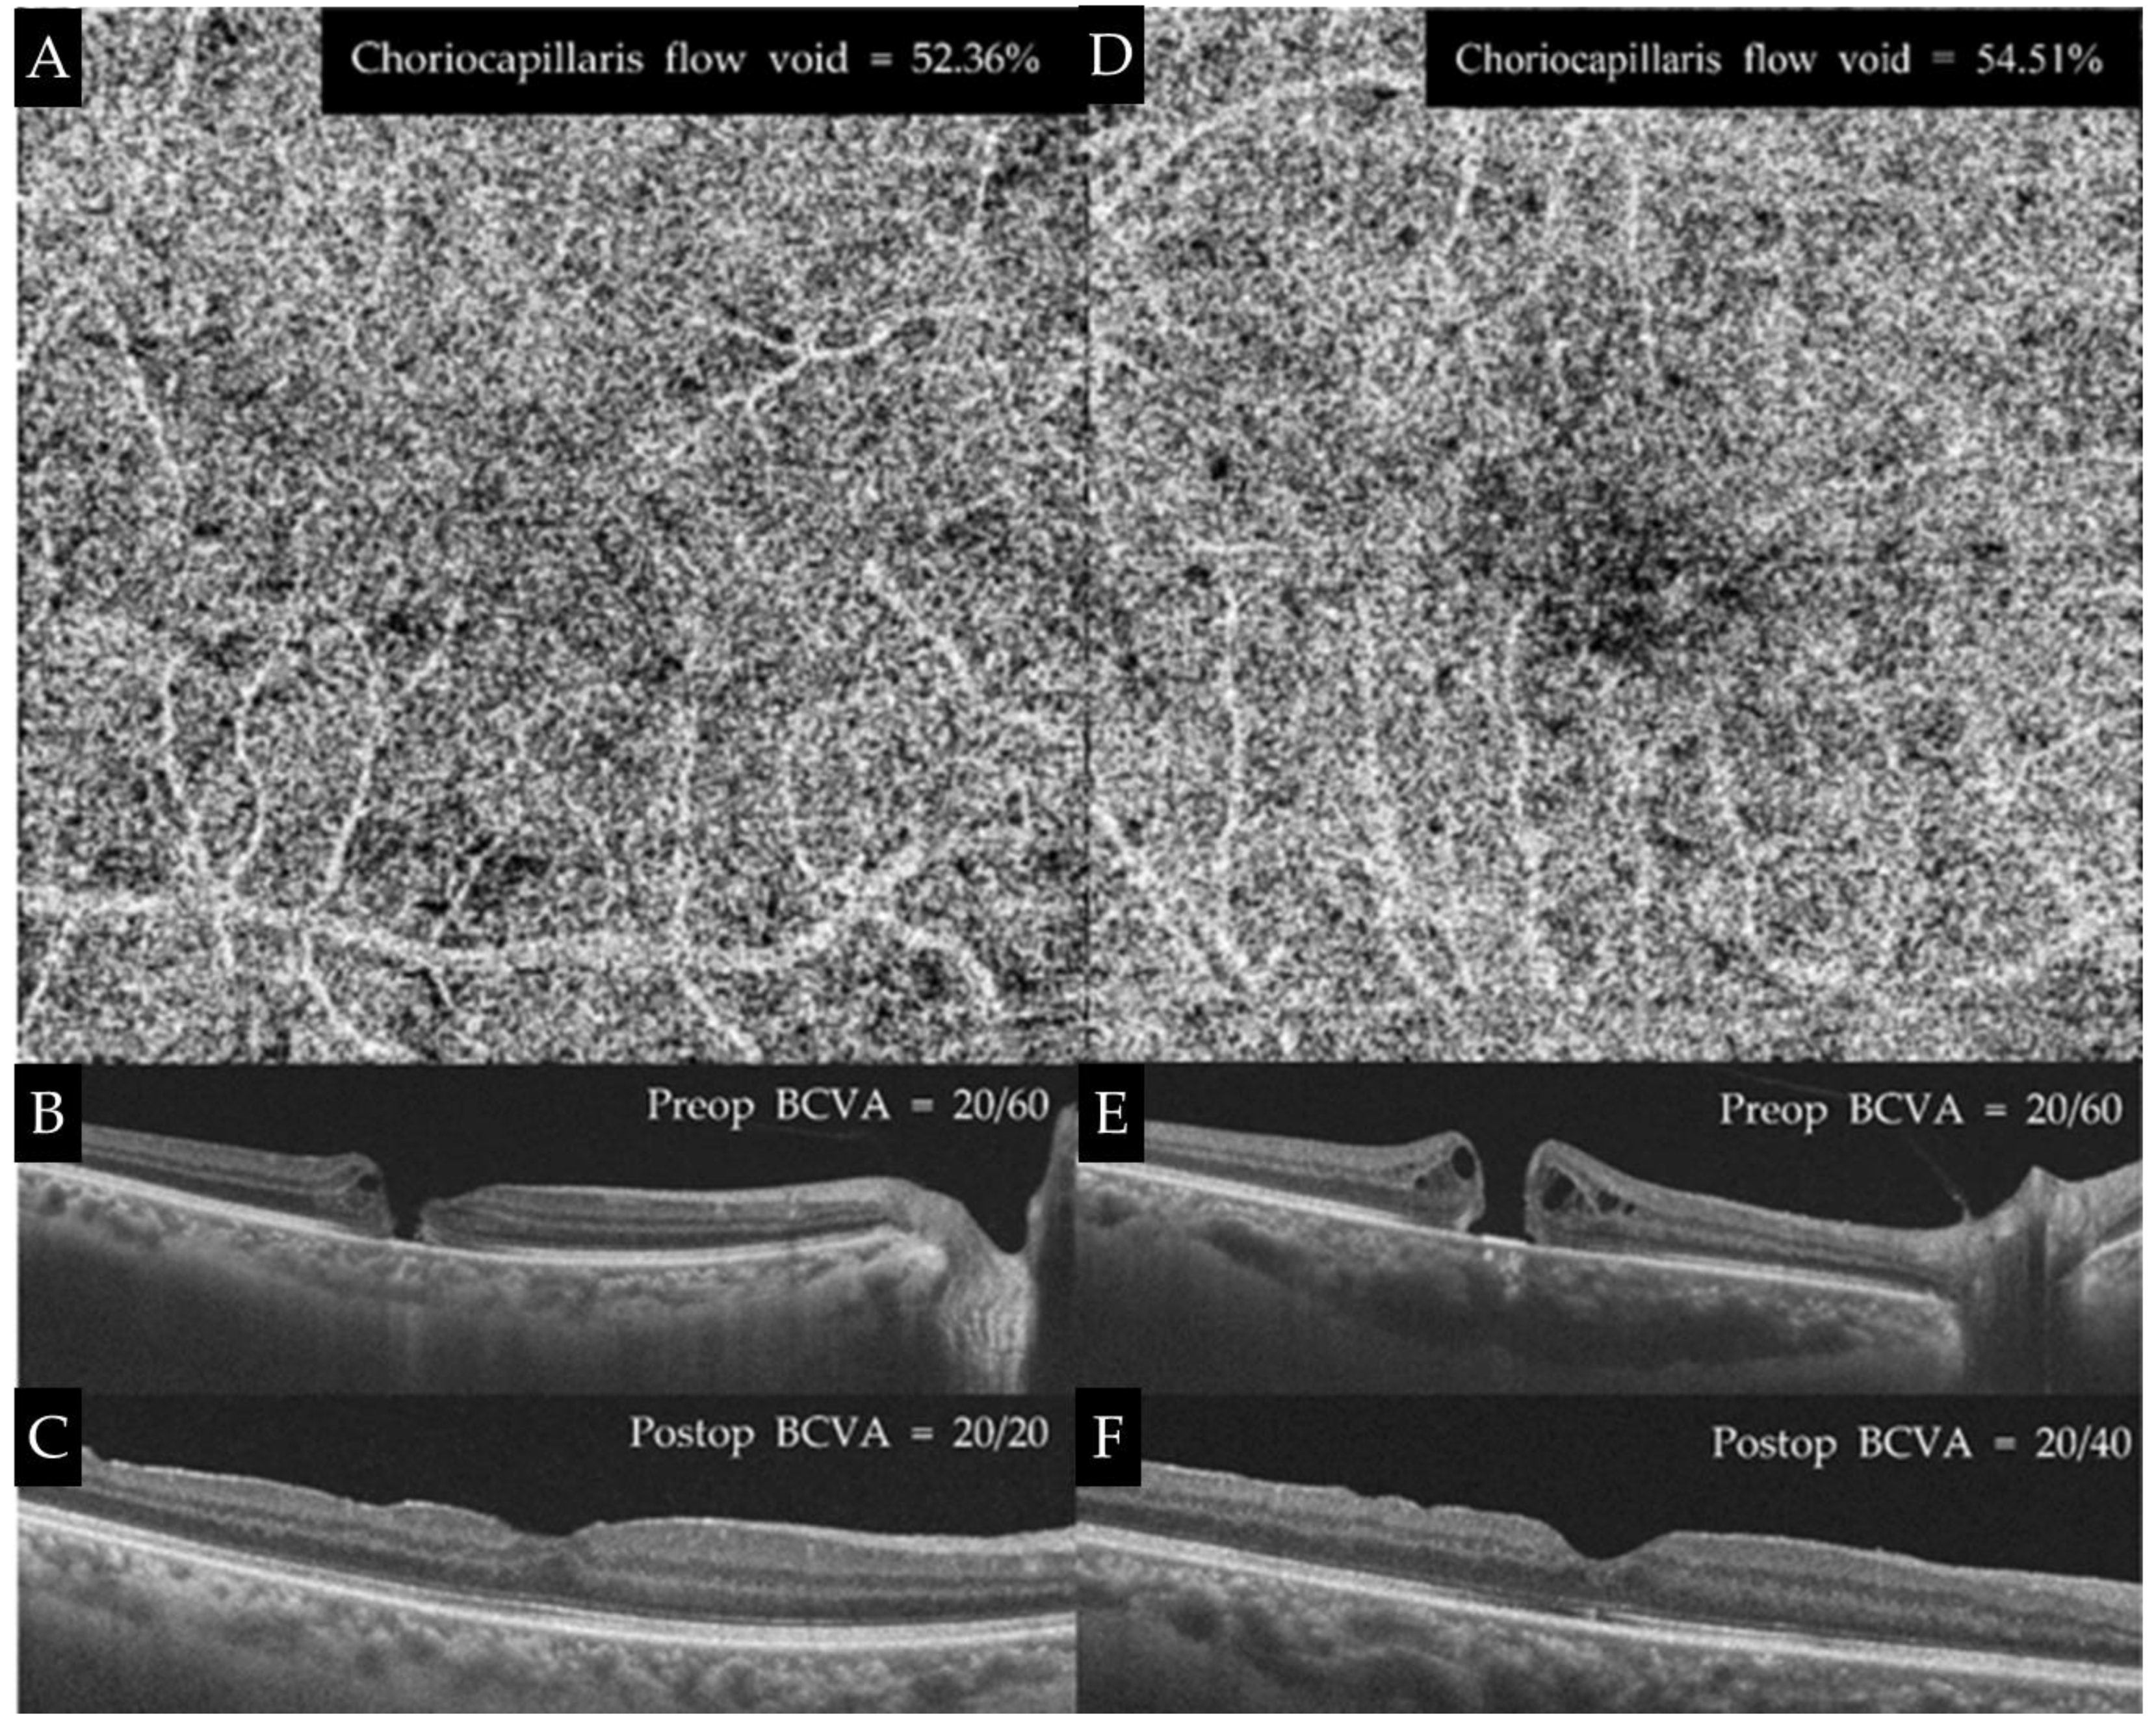

| Choriocapillaris flow void (%) | Center | 50.07 ± 3.35 | 48.18 ± 3.44 | 48.05 ± 3.88 | 0.027 | 0.007 | 0.146 |

| Total | 54.25 ± 1.04 | 53.18 ± 1.09 | 52.36 ± 1.05 | 0.81 | 0.031 | 0.117 | |

| Choriocapillaris flow void (%) | Center | 48.81 ± 2.90 | 49.43 ± 2.62 | 0.386 | 47.78 ± 3.26 | 49.13 ± 5.76 | 0.374 | 0.311 |

| total | 52.27 ± 0.92 | 51.94 ± 0.44 | 0.169 | 54.11 ± 1.01 | 51.73 ± 1.15 | 0.022 | 0.638 | |

| Choriocapillaris flow void (%) | Center | 50.25 ± 5.95 | 48.81 ± 2.90 | 0.018 | 49.92 ± 9.94 | 47.78 ± 3.26 | 0.249 | 0.681 |

| total | 51.67 ± 0.92 | 52.27 ± 0.92 | 0.236 | 51.00 ± 1.12 | 54.11 ± 1.01 | 0.139 | 0.299 | |

| Choriocapillaris flow void | −0.029 | 0.974 | 0.378 | 0.018 |